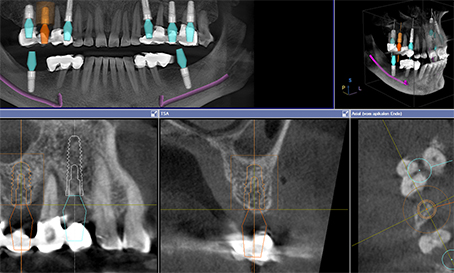

ÜBERWEISUNG ZUR DENTALEN VOLUMEN-TOMOGRAPHIE

Als eine der wenigen Zahnarztpraxen in Nürnberg verfügen wir über die Möglichkeit digitale Volumenaufnahmen der Kieferstrukturen zu erstellen. Diese helfen neben der exakten Planung für implantologische Eingriffe auch bei komplizierten Wurzelbehandlungen, nervnaher Lage von Weißheitszähnen und vielen anderen anspruchsvollen anatomischen Fragestellungen.

Für Überweiser- bzw. Zahnarztpraxen, die nicht über diese technische Möglichkeit verfügen, bieten wir diesen Service zu besonders günstigen Konditionen an.